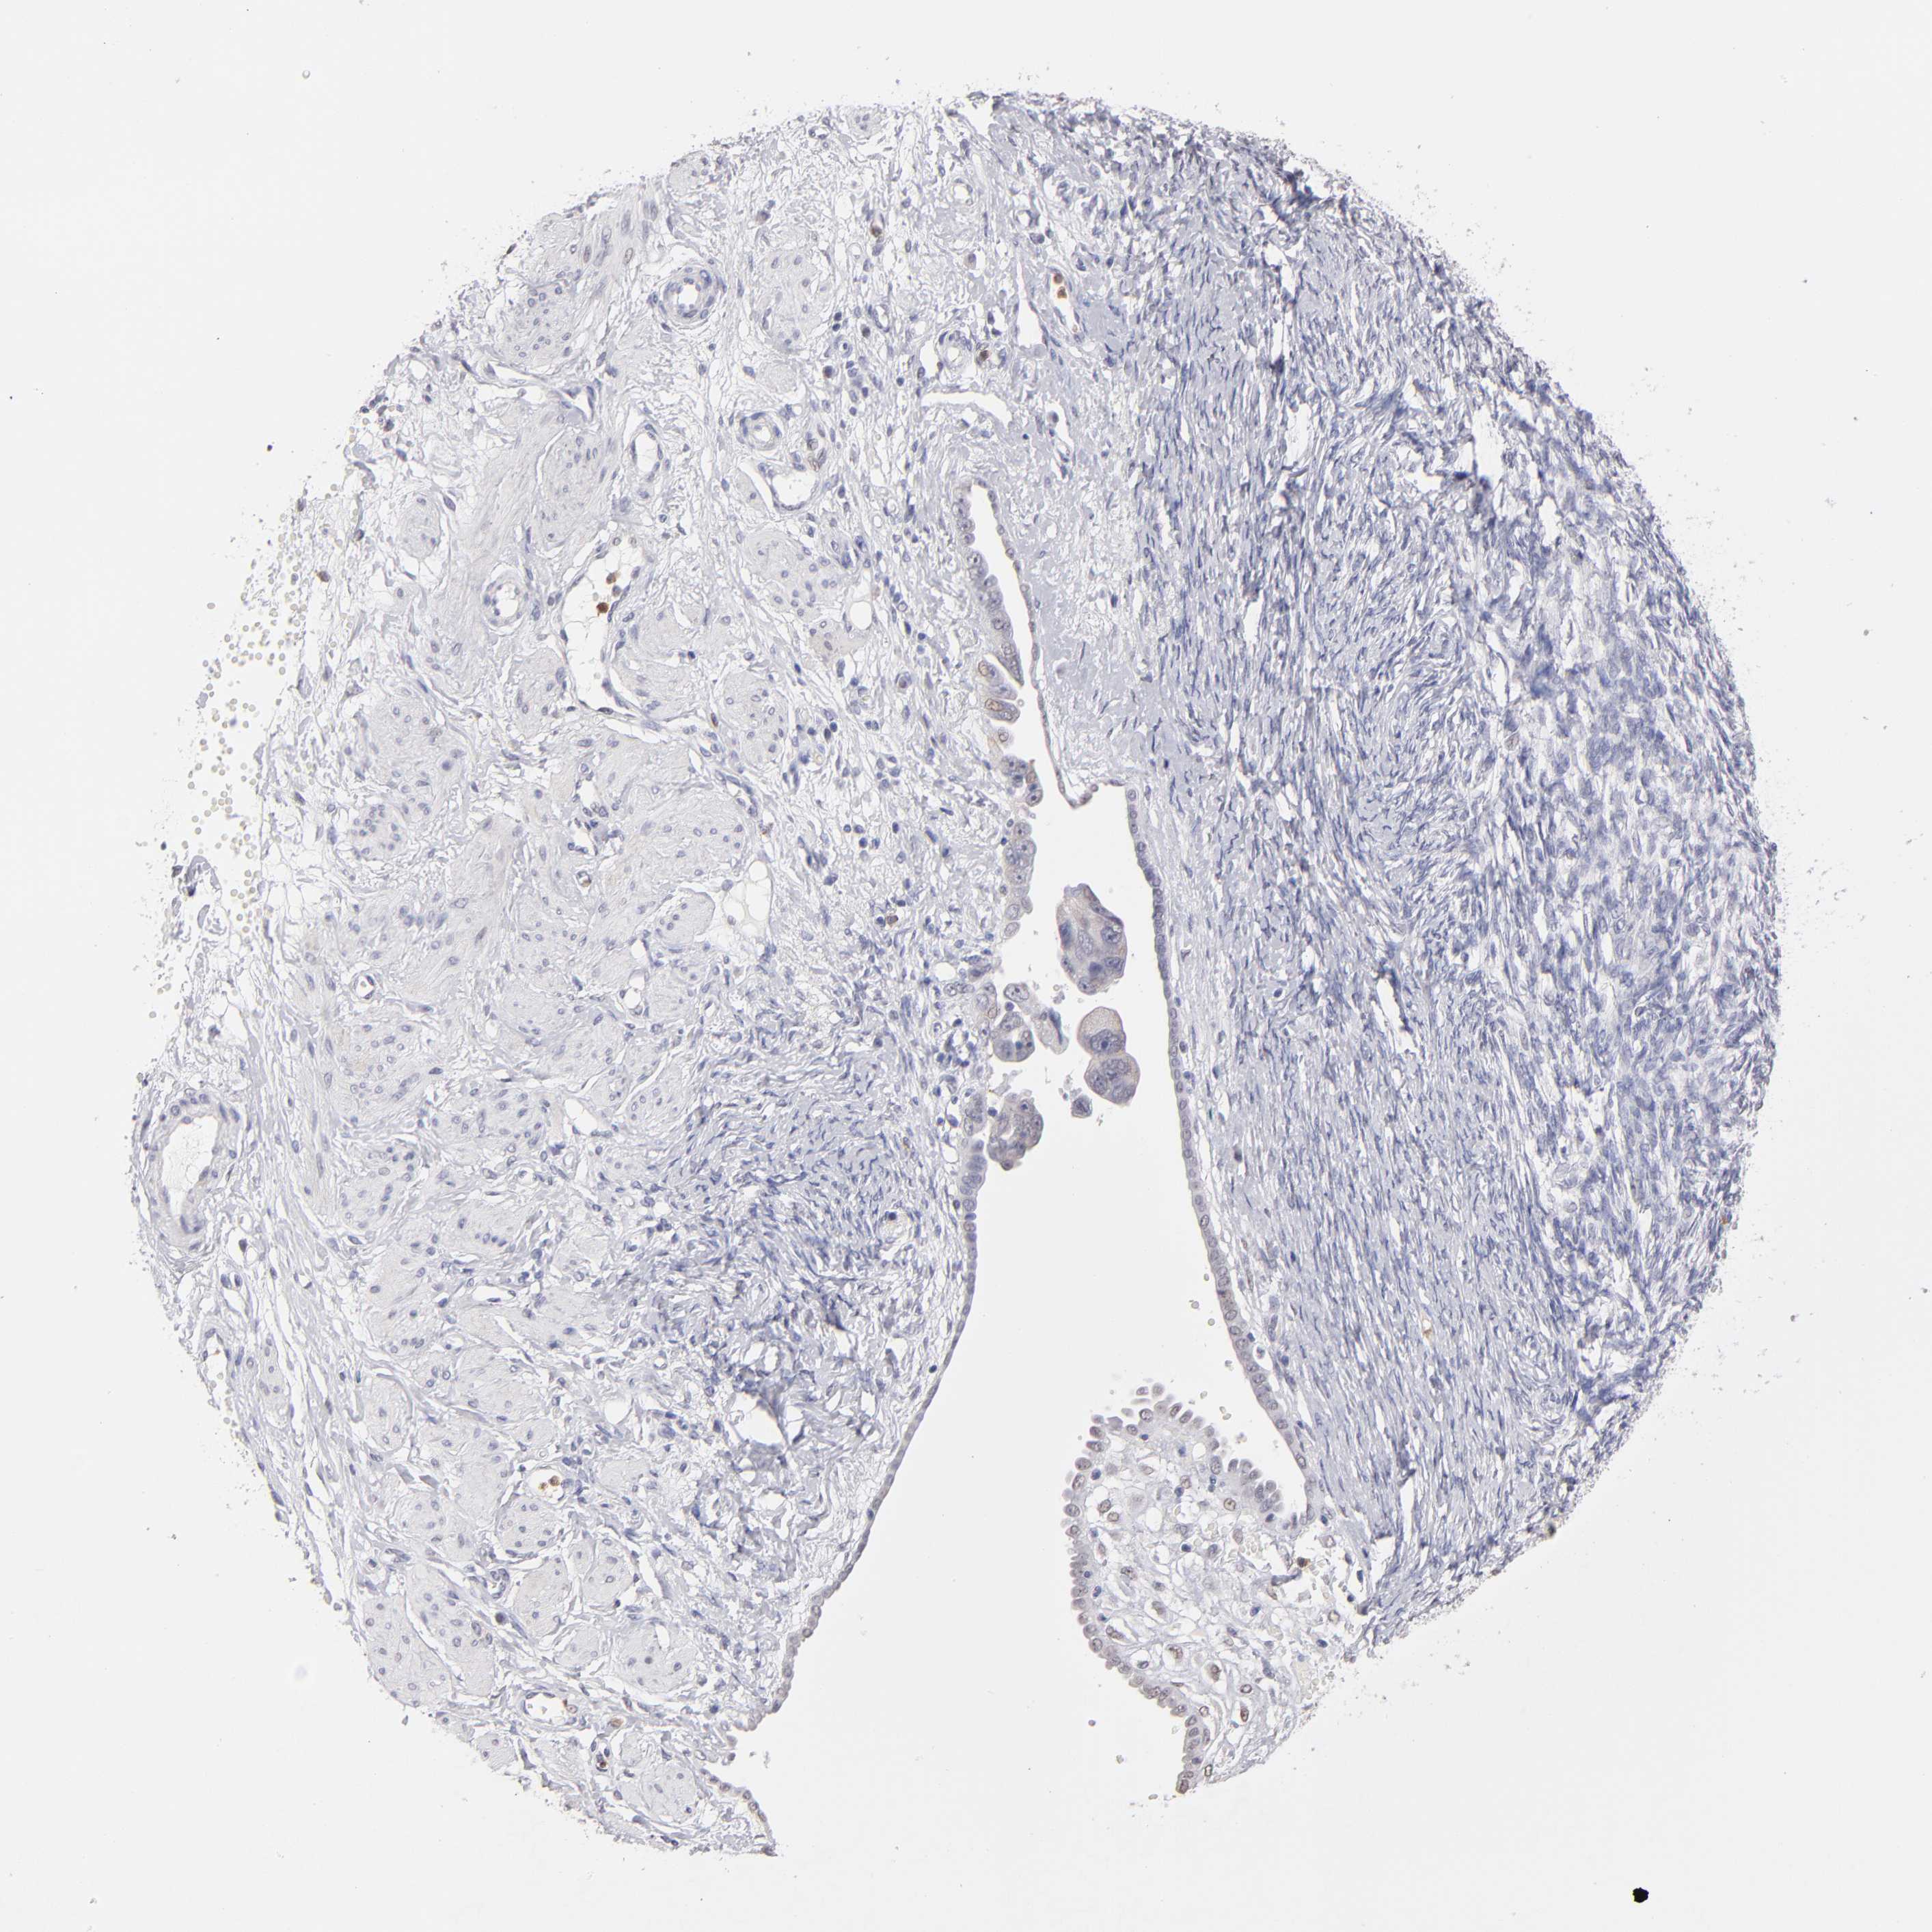

OVARIAN CANCER - Protein expressioni

A mouse-over function shows sample information and annotation data. Click on an image to view it in a full screen mode. Samples can be filtered based on level of antibody staining by selecting one or several of the following categories: high, medium, low and not detected. The assay and annotation is described here.

Note that samples used for immunohistochemistry by the Human Protein Atlas do not correspond to samples in the TCGA dataset.

Antibody stainingi

Antibody staining in the annotated cell types in the current human tissue is reported as not detected, low, medium, or high, based on conventional immunohistochemistry profiling in selected tissues. This score is based on the combination of the staining intensity and fraction of stained cells.

Each image is clickable and will lead to virtual microscopy that enables deeper exploration of all samples and also displays staining intensity scores, fraction scores and subcellular localization as well as patient and tissue information for each sample.

Antibody HPA002270

Cystadenocarcinoma, serous, NOS

Cystadenocarcinoma, mucinous, NOS

Carcinoma, endometroid